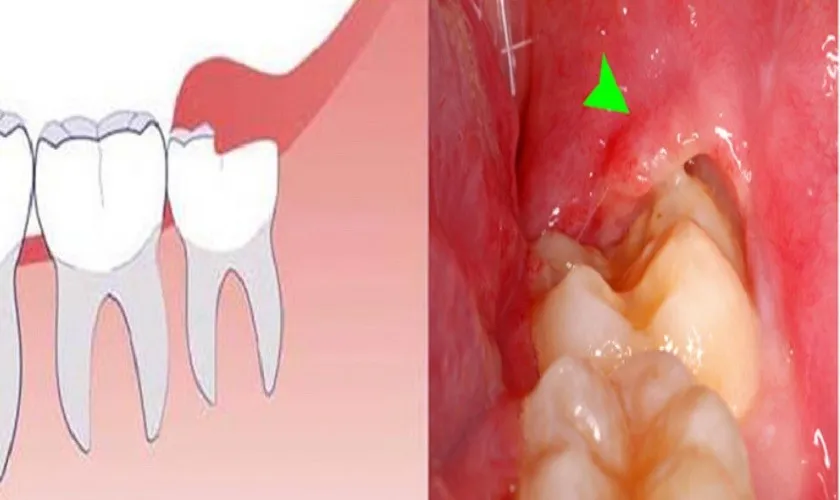

Khi nào cần nhổ răng khôn là câu hỏi mà nhiều người thắc mắc, bởi lẽ răng khôn hay còn gọi là răng số 8 thường gây